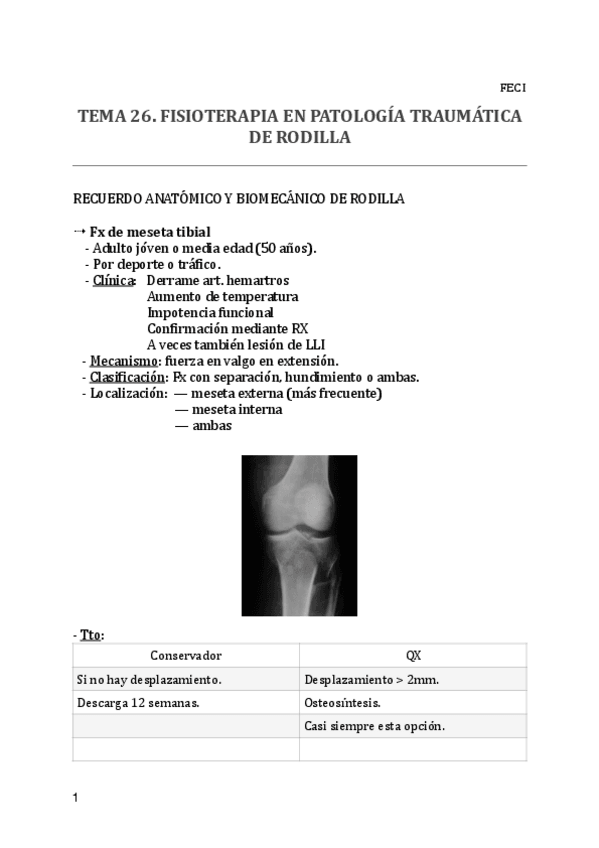

He publicado nuevos apuntes de 2º Fisioterapia en Especialidades Clínicas I: 26.-F-en-patologia-traumatica-de-rodilla.pdf